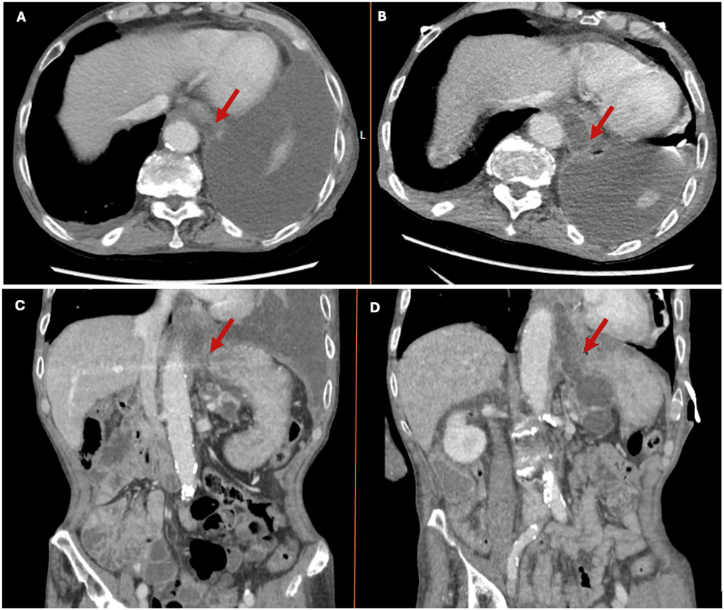

Pancreatopleural fistulas, rare complications of chronic pancreatitis, are often overlooked in the initial differential diagnoses of pleural effusions, resulting in delayed diagnosis and management. We present the case of an elderly male with recurrent pleural effusion and a history of chronic pancreatitis. Diagnostic challenges arose, with the initial misdiagnosis as pneumonia. Elevated pleural fluid amylase levels (11,370U/L) along with imaging findings led to the diagnosis of a pancreatopleural fistula. This case underscores the importance of considering uncommon etiologies in pleural effusions and highlights the significance of high pleural fluid amylase levels in diagnosing pancreatopleural fistulas.